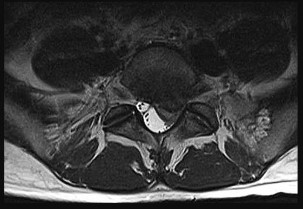

A 32-year-old male is involved in a high-speed motor vehicle collision and arrives with a unilateral C6-C7 facet dislocation and a dense C6 radiculopathy. Closed reduction with cranial tongs is attempted in the awake patient but is unsuccessful. What is the most appropriate next step in management?

- Obtain an urgent MRI of the cervical spine followed by surgical intervention

Correct Answer: Obtain an urgent MRI of the cervical spine followed by surgical intervention

Explanation:

In cases of cervical facet dislocation where awake closed reduction fails, or in a patient who cannot be examined (e.g., obtunded), an MRI of the cervical spine is the standard of care before proceeding to open reduction. The MRI is essential to identify the presence of a herniated intervertebral disc. If an anterior disc herniation is present, a posterior-only open reduction poses a significant risk of extruding the disc further into the spinal canal, potentially causing a catastrophic spinal cord injury. Therefore, MRI dictates whether an anterior approach (to remove the disc before reduction) is required.